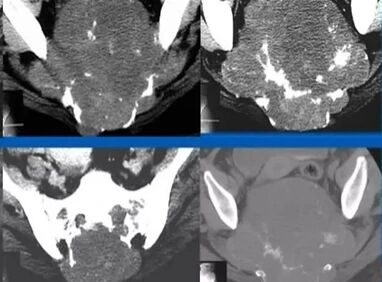

二、患者男,51岁,骶尾部脊索瘤,2022年5月23日行重离子治疗。

治疗前2022年5月6日 治疗后2024年8月12日